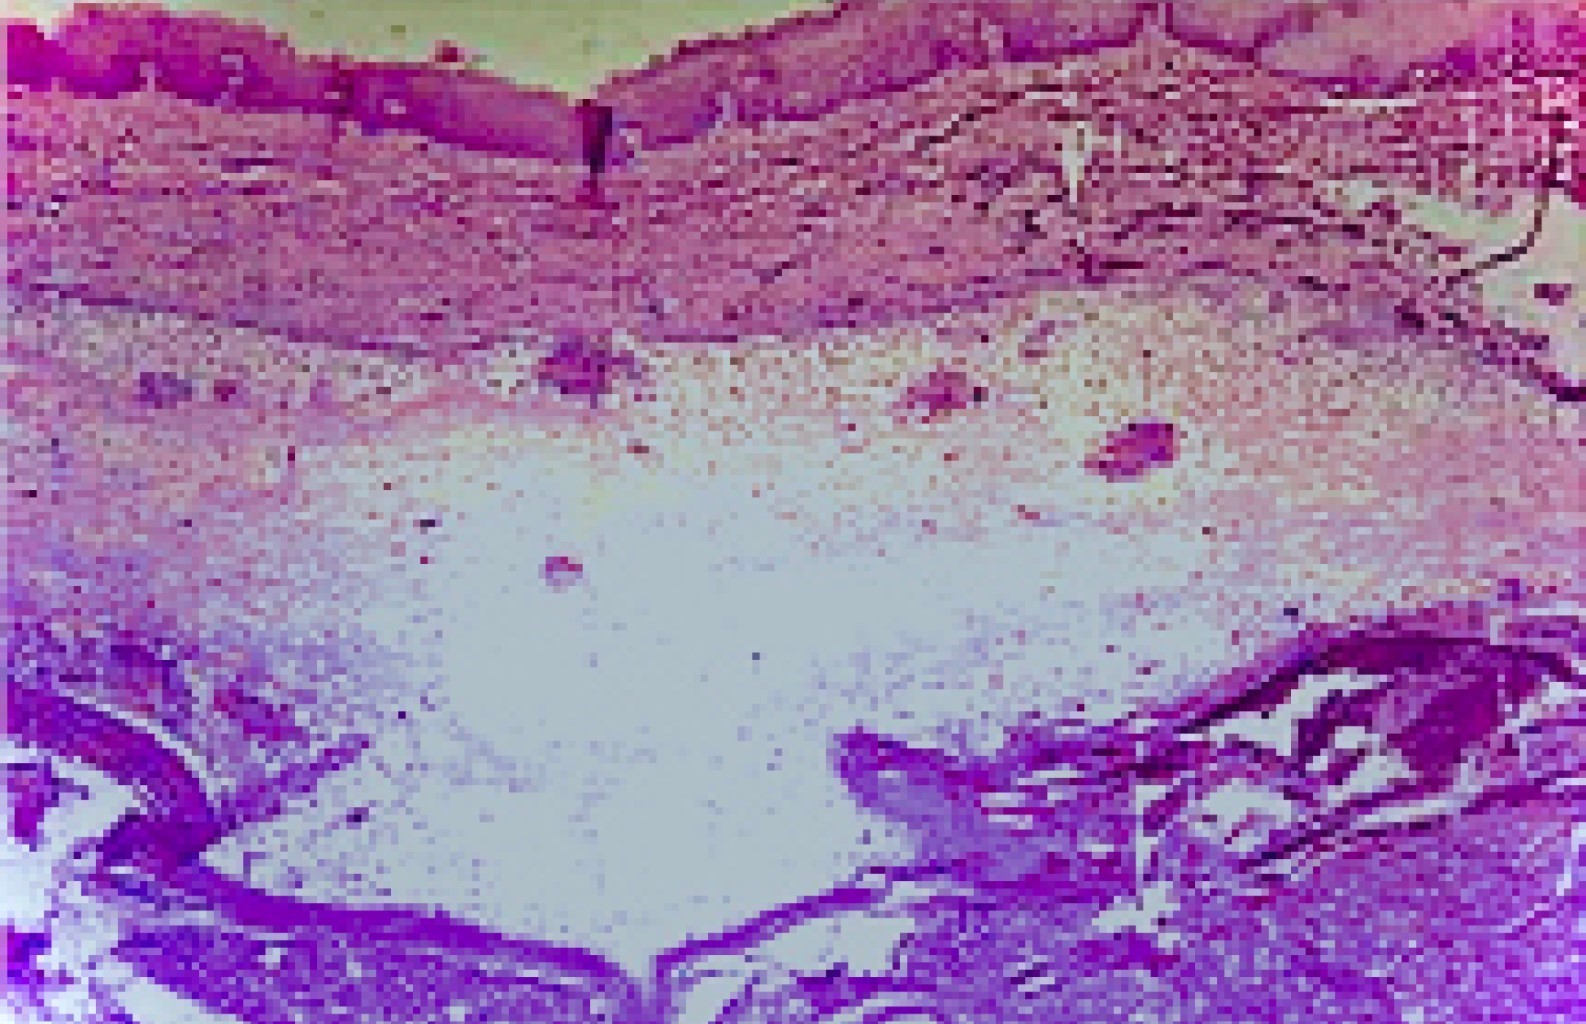

La muestra del estudio incluyó los materiales biológicos embebidos en parafina procesados mediante la técnica histotecnológica convencional, y teñidos con la técnica de hematoxilina-eosina. Las láminas debidamente teñidas permitieron su estudio descriptivo con microscopia óptica, e identificación diagnóstica, registrándose en protocolos y libros de ingreso del SAPyC.

Durante el periodo evaluado (1997-2017), se recibieron y procesaron 14,186 muestras en el SAPyC del Hospital Pediátrico "Juan Pablo II", de los cuales 63 casos correspondieron a lesiones de las glándulas salivales. Cuarenta y siete tuvieron diagnóstico histopatológico de mucocele (Figuras 1 y 2), representando el 74.6% de las lesiones de glándulas salivales, siendo por lo tanto la patología más frecuente en la población estudiada (Tabla 1).